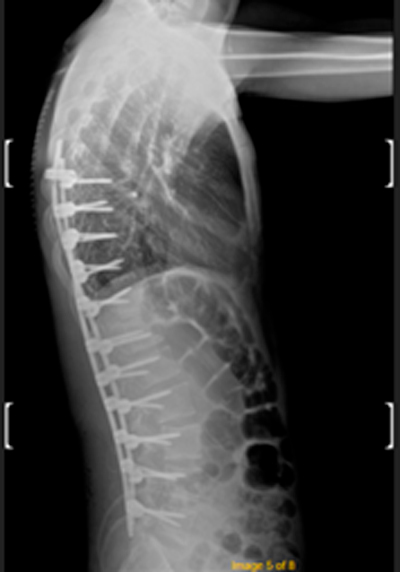

DIAGNOSI:

IPERCIFOSI DORSALE GRAVE

Radiografia dorsale pre operatoria

Intervento chirurgico eseguito:

STABILIZZAZIONE DORSO – LOMBARE CON OSTEOTOMIE CORRETTIVE

Radiografia dorsale post-operatoria